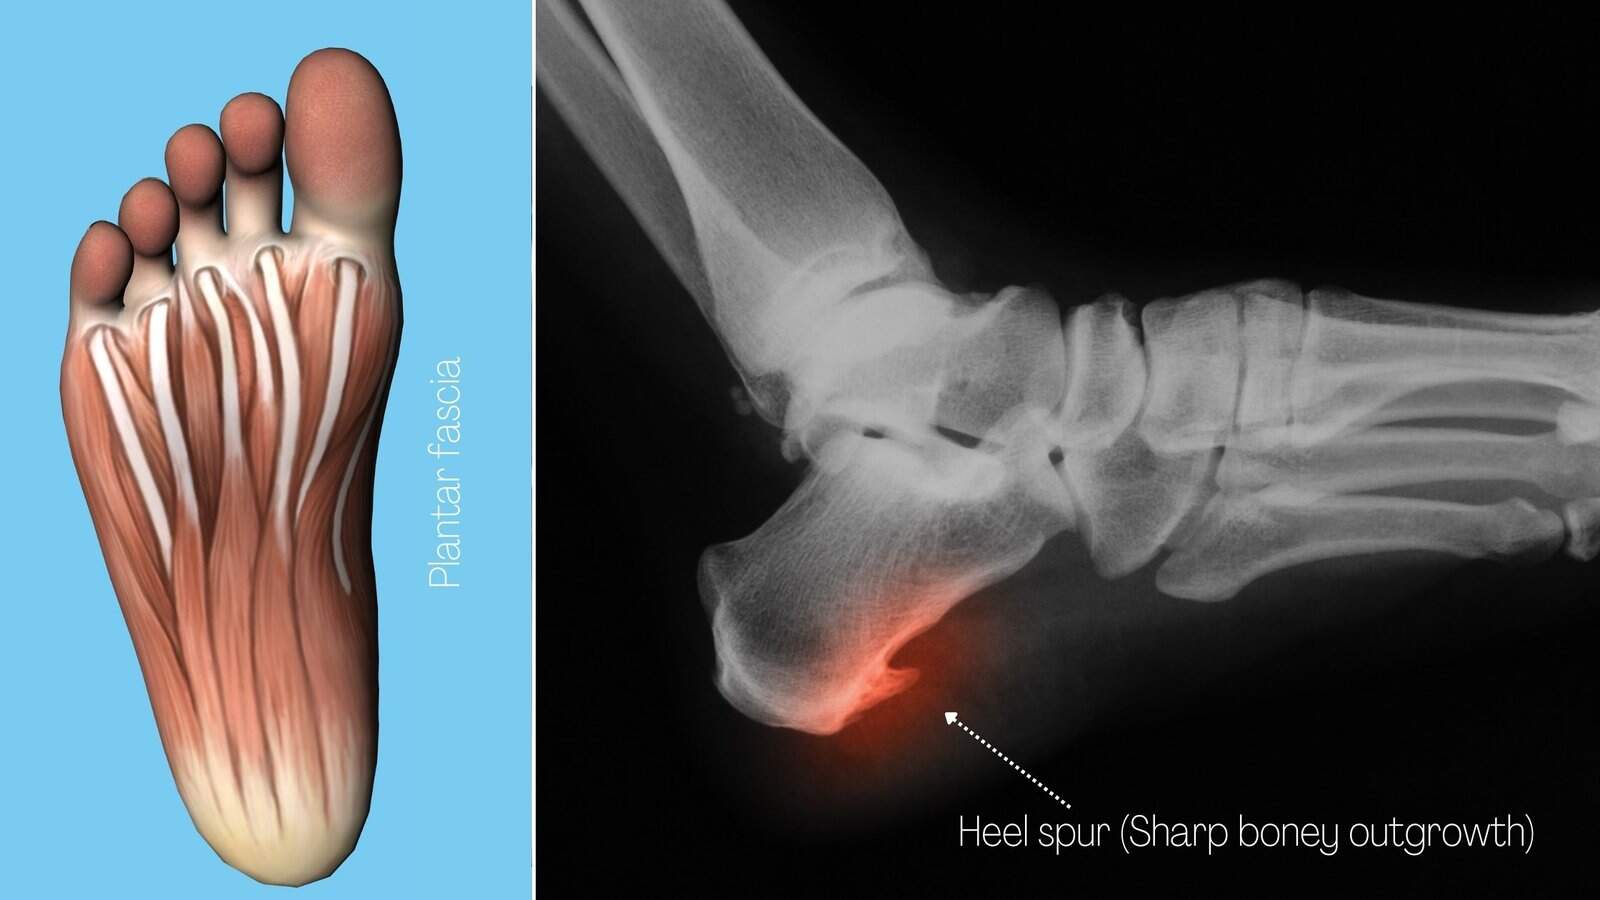

What Is Sharp Pain In Heel . Plantar fasciitis is a foot condition characterized by sharp, stabbing heel pain that typically occurs when a person gets out of bed in the morning or stands up after sitting for a. Pain on the bottom of the foot, near the heel. The most common symptoms of plantar fasciitis include: This is the most prevalent and telltale sign of plantar fasciitis. The most common causes of heel pain are plantar fasciitis, which affects the bottom of the heel, and achilles tendinitis, which. For example, pain on the side of the heel may be due to. Heel pain can have a number of causes, and specific features of the pain can help a healthcare provider diagnose the pain. Your plantar fascia is a tight, thick tissue that connects your heel bone to your toes. Plantar fasciitis occurs when the. Heel pain is a very common foot and ankle problem. You might experience pain, soreness or tenderness anywhere in your.

Your plantar fascia is a tight, thick tissue that connects your heel bone to your toes. The most common causes of heel pain are plantar fasciitis, which affects the bottom of the heel, and achilles tendinitis, which. Pain on the bottom of the foot, near the heel. Plantar fasciitis occurs when the. Plantar fasciitis is a foot condition characterized by sharp, stabbing heel pain that typically occurs when a person gets out of bed in the morning or stands up after sitting for a. The most common symptoms of plantar fasciitis include: For example, pain on the side of the heel may be due to. This is the most prevalent and telltale sign of plantar fasciitis. Heel pain can have a number of causes, and specific features of the pain can help a healthcare provider diagnose the pain. You might experience pain, soreness or tenderness anywhere in your.